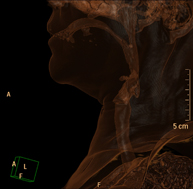

- TC Cuello Prueba radiológica que consiste en obtener imágenes del cuello de alta definición anatómica mediante el empleo de un equipo de TC (Tomografía Computarizada). Indicaciones: estudio de tiroides, control de tumores tratados, estudio de ganglios, infecciones y abscesos. Prueba radiológica que consiste en obtener imágenes del cuello de alta definición anatómica mediante el empleo de un equipo de TC (Tomografía Computarizada). Indicaciones: estudio de tiroides, control de tumores tratados, estudio de ganglios, infecciones y abscesos.

- TC Laringe Prueba radiológica que consiste en obtener imágenes de la laringe de alta definición anatómica mediante el empleo de un equipo de TC (Tomografía Computarizada). Indicaciones: afonía súbita o crónica, dificultad respiratoria. Prueba radiológica que consiste en obtener imágenes de la laringe de alta definición anatómica mediante el empleo de un equipo de TC (Tomografía Computarizada). Indicaciones: afonía súbita o crónica, dificultad respiratoria.